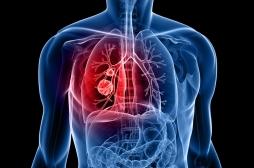

tumeur

LES MALADIES

J'AI MAL